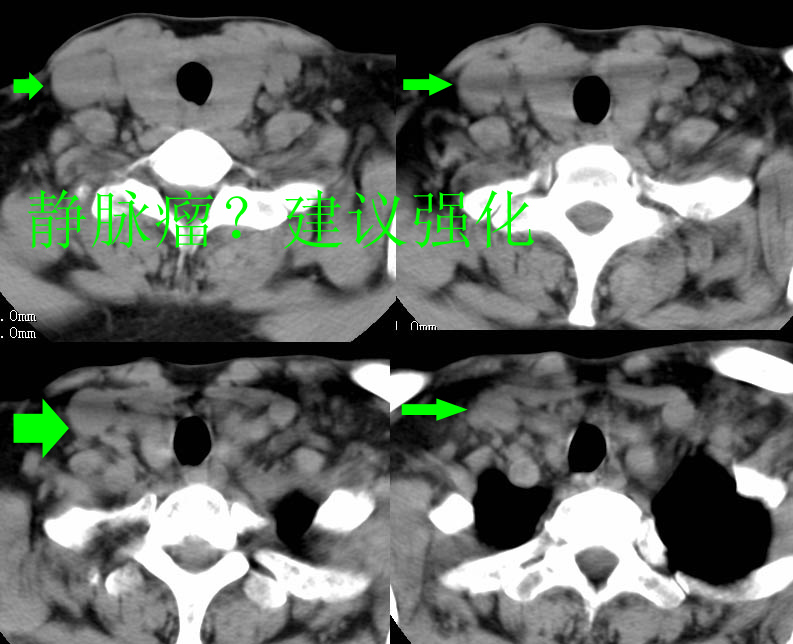

以下是引用zhangzhongshou在2007-4-23 12:41:00的发言:[br]甲状腺弥漫性肿大,密度减低,符合甲状腺炎ct表现,建议进一步检查